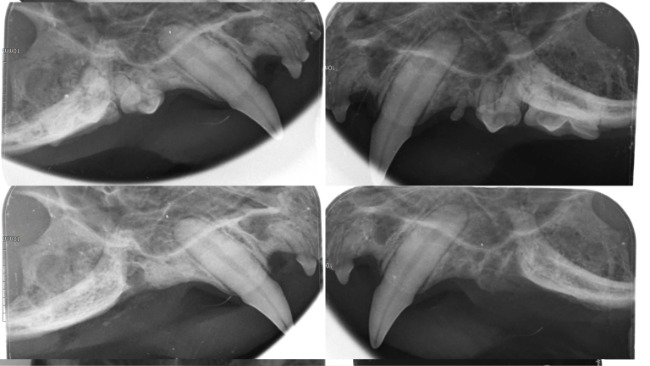

11/06-Został przeprowadzony zabieg stomatologiczny, zgodnie z założeniami Łobuz miał usunięte wszystkie zęby policzkowe oraz sieczne. Na RTG uzębienia uwidoczniono spory zanik kości zębodołu oraz liczne zmiany resorpcyjne (FORL). Od wczoraj dzięki Wam Łobuz się może cieszyć życiem bez bólu!!!